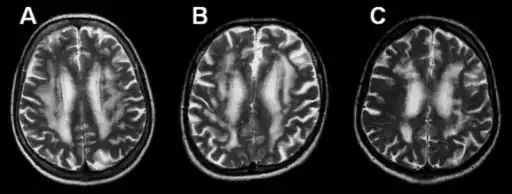

Binswanger's disease can usually be diagnosed with a computerized tomography scan, magnetic resonance imaging, and proton magnetic resonance spectrography in addition to clinical examination. Indications include infarctions, lesions, or loss of intensity of central white matter and enlargement of ventricles, and leukoaraiosis. A Mini–Mental State Examination has been created to quickly assess cognitive impairment and serves as a screening test for dementia across different cultures.

Leukoaraiosis refers to the imaging finding of white matter changes that are common in Binswanger disease. However, leukoaraiosis can be found in many different diseases and even in normal patients, especially in people older than 65 years of age.[6]

There is controversy whether leukoaraiosis and mental deterioration actually have a cause and effect relationship. Recent research is showing that different types of leukoaraiosis can affect the brain differently, and that proton magnetic resonance spectroscopy would be able to distinguish the different types more effectively and better diagnosis and treat the issue.[10] Because of this information, white matter changes indicated by magnetic resonance imaging or computerized tomography cannot alone diagnose Binswanger disease, but can aid to a bigger picture in the diagnosis process. There are many diseases similar to Binswanger's disease including CADASIL syndrome and Alzheimer's disease, which makes this specific type of white matter damage hard to diagnose.[6] Binswanger disease is best when diagnosed of a team by experts including a neurologist and psychiatrist to rule out other psychological or neurological problems.[4] Because doctors must successfully detect enough white matter alterations to accompany dementia as well as an appropriate level of dementia, two separate technological systems are needed in the diagnosing process.

Much of the major research today is done on finding better and more efficient ways to diagnose this disease. Many researchers have divided the magnetic resonance imaging of the brain into different sections or quadrants. A score is given to each section depending on how severe the white matter atrophy or leukoaraiosis is. Research has shown that the higher these scores, the more of a decrease in processing speed, executive functions, and motor learning tasks.[15][16] Other researchers have begun using computers to calculate the percentage of white matter atrophy by counting the hyper-intense pixels of the magnetic resonance images. These and similar reports show a correlation between the amount of white matter alterations and the decline of psychomotor functions, reduced performance on attention and executive control.[17][18] One recent type of technology is called susceptibility weighted imaging (SWI) which is a magnetic resonance technique which has an unusually high degree of sensitivity and can better detect white matter alterations.[19]